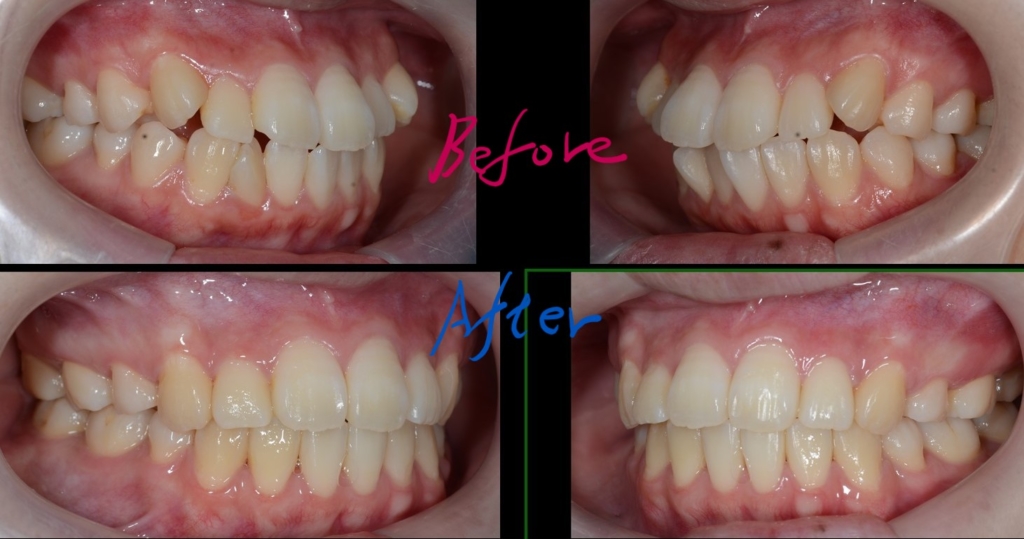

ついでに、歯並びの比較です

上段が矯正治療前、下段が矯正治療後

矯正治療の結果、狙い通りに口元をスッキリさせることが出来ました。

お口を閉じるのにも「力」が要らなくなり、楽に閉じれるようになった!と喜んでもらいました。

また、Eラインに収めることは出来ませんでしたが、患者さん的には引っ込み過ぎるは嫌なので、元々あった口元の突出感も無くなり、このくらいがちょうど良い!とのこと。